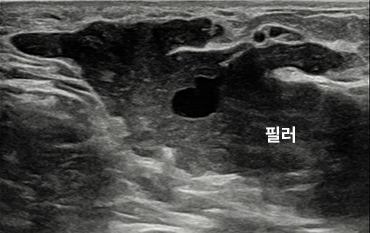

가슴필러, img img

꼭 제거해야 하는 이유

가슴에 주입된 필러는 무조건 제거해야 합니다.

식약처에서는 유방확대의 목적으로 어떤 종류의 필러도 허가해 준 적이 없기 때문입니다.

필러는 어떤 외피에 싸여져 있지 않은 채, 무작위로 가슴 내에 주사기를 통해서 주입되기 때문에

어디로 퍼질지 모르며 실제로 배, 사타구니까지 흘러내리는 경우도 있습니다.

• img

가슴 아래로 흘러내린 필러

옆구리까지 흘러내린 필러

가슴필러 제거 수술 방법

• img img

01

초음파 검사를 통해

필러의 위치 파악

초음파로 보면 큰 덩어리의 필러가 모여 있기 때문에 모두 제거하면 되지만

문제는 유방조직에 끈끈하게 붙어 있는 필러입니다.

이를 무리하게 긁어내면 본인의 정상 유방조직에 손상이 갈 수 있으므로

유방조직의 손상은 최소화 시키면서 필러를 최대한 제거할 수 있는

섬세한 기술

이 필요합니다.

• 필러가 근육 위에 뭉쳐져 있는 상태

img img

<제거 수술 전>

• 필러가 깨끗하게 제거 된 상태

img

<제거 수술 후>